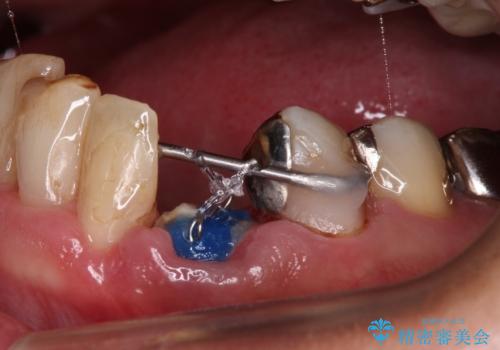

当該歯である犬歯は歯根が長く、安易に抜歯することはおすすめできないため、まずは部分矯正により歯根を引っ張り出し、その後歯周外科処置により歯槽骨や歯肉の状態を整え、最終的にはオールセラミッククラウンにて補綴治療を行うこととしました。

矯正治療中は汚れが溜まりやすく、歯肉からの出血が続きましたが、最終的には歯を保存して安定した状態で補綴治療を行うことができました。